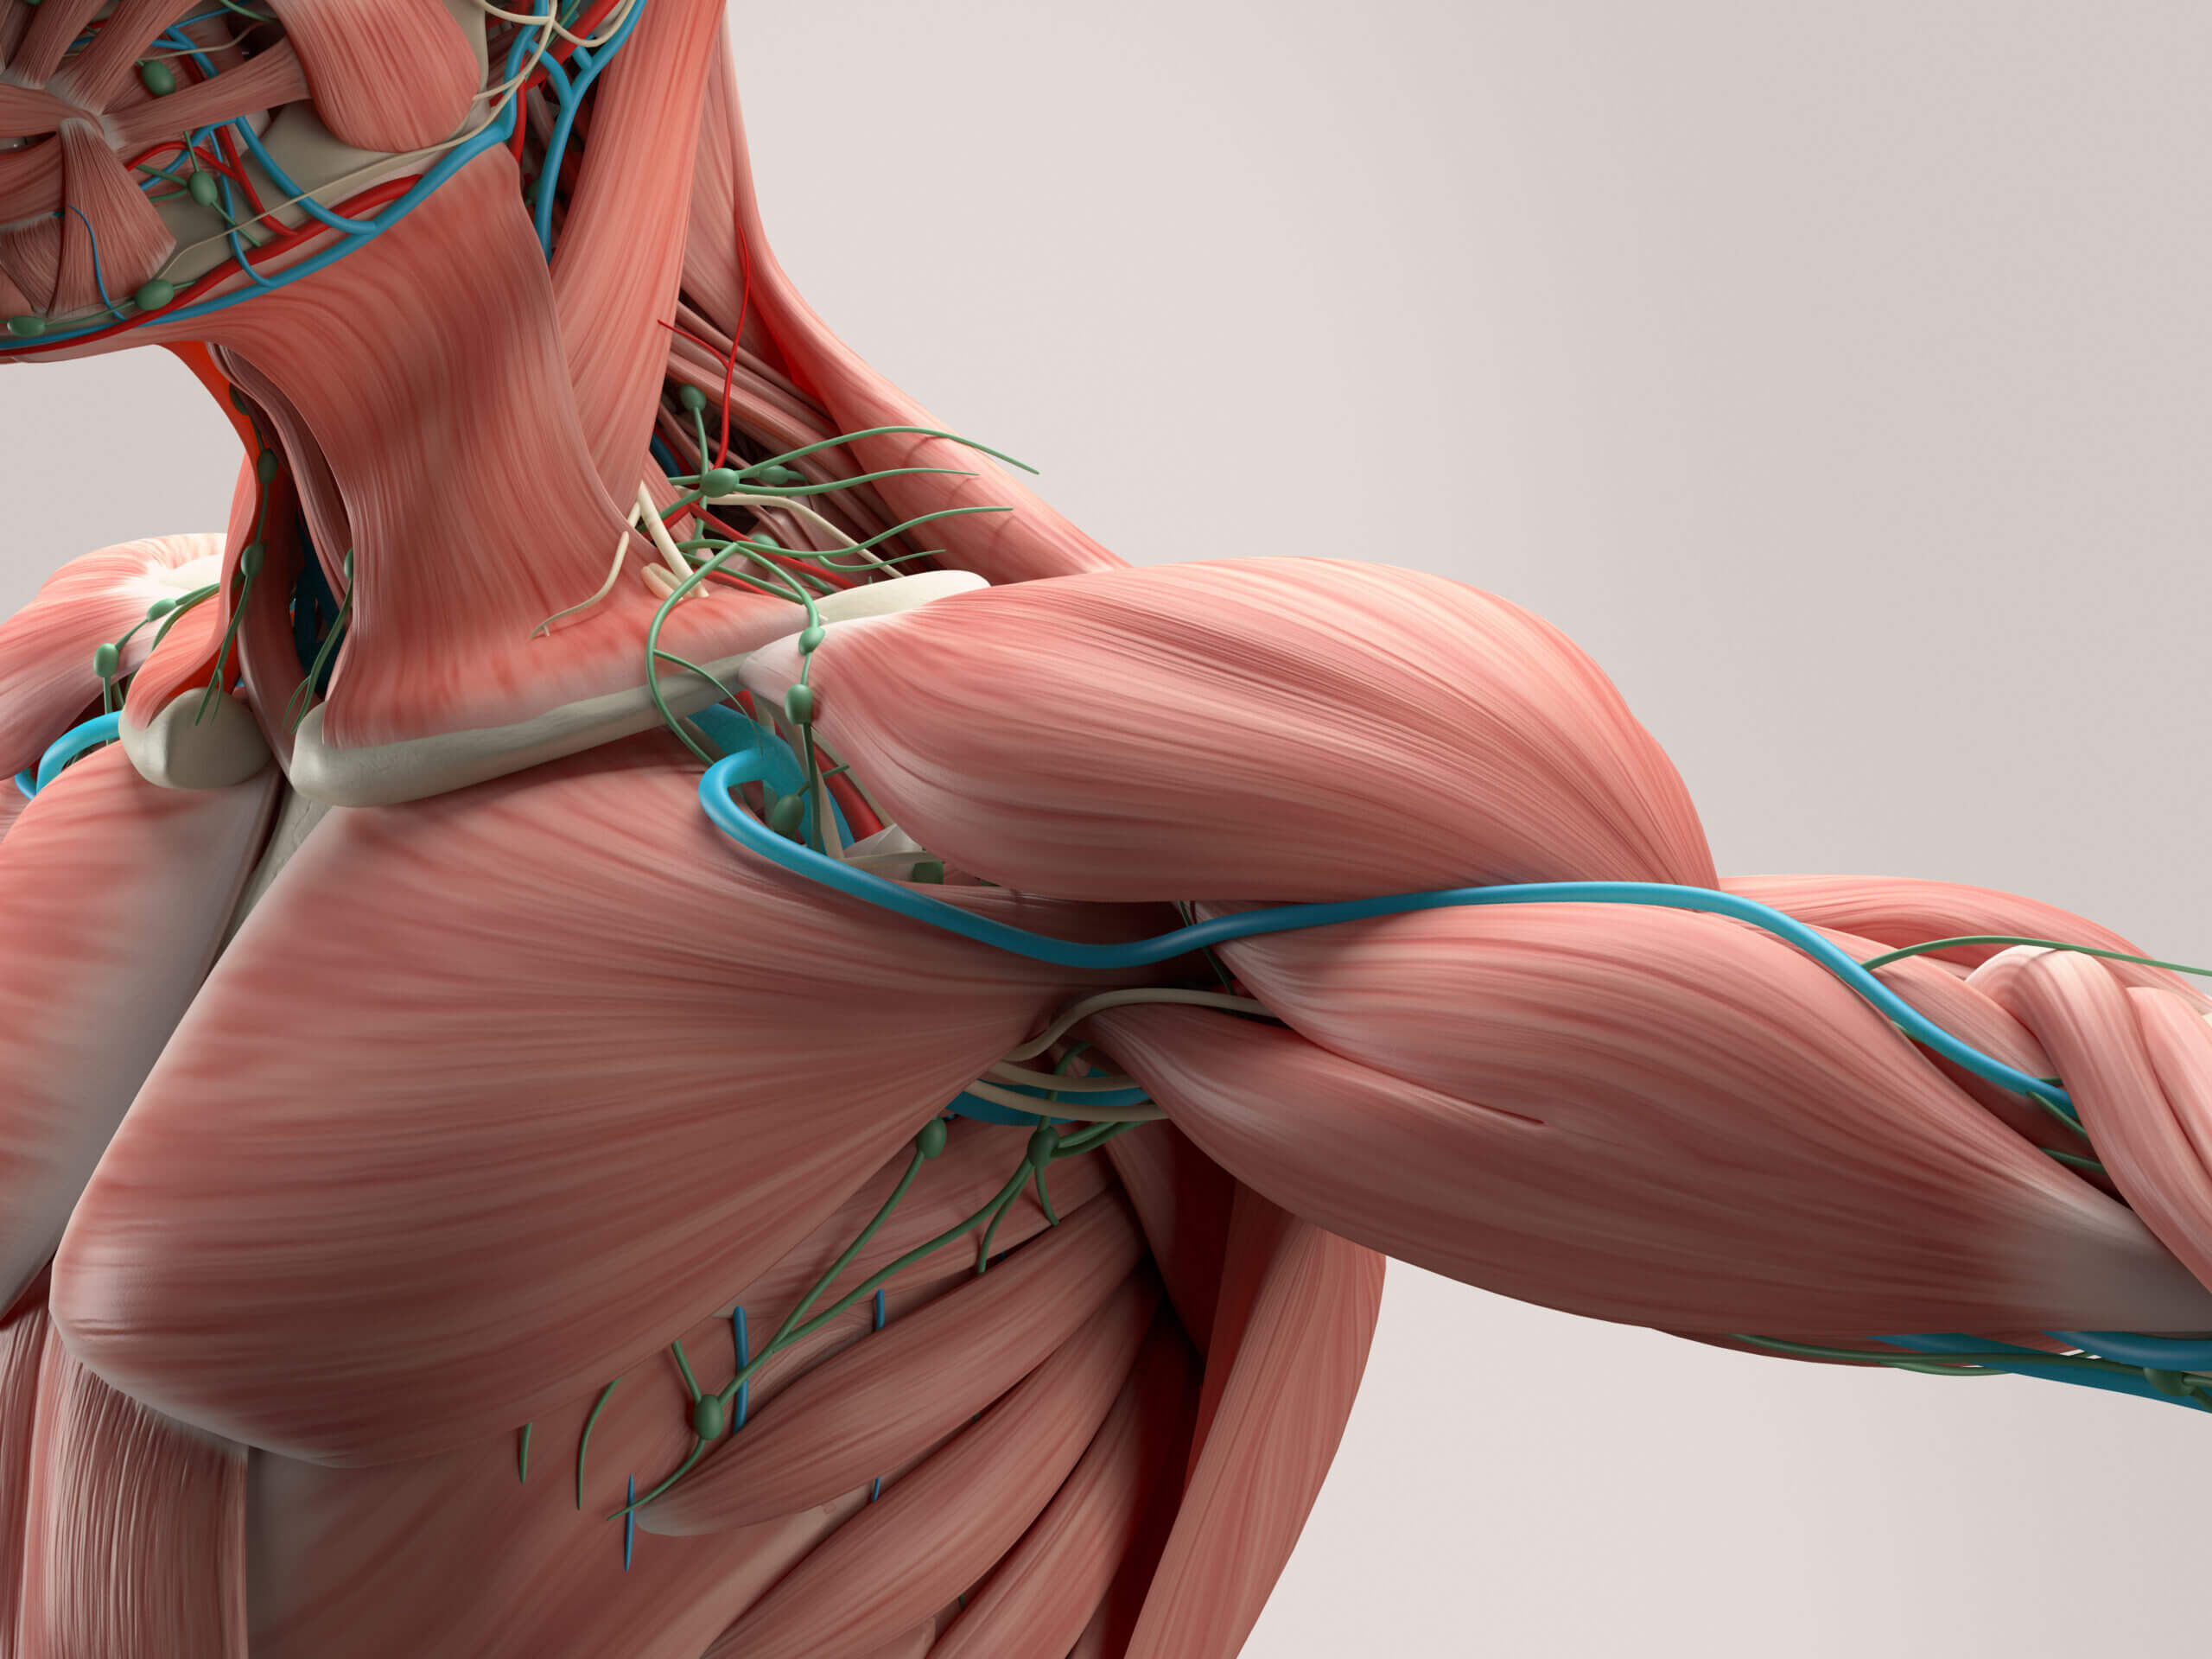

قیمت: 108٬000 تومان - دسته بندی فایل: پاورپوینتپاورپوینت ساختمان و کار عضله

فروش ویژه پاورپوینت حرفه ای ساختمان و کار عضله با تخفیف استثنایی فقط 49 هزار تومان تعداد اسلاید: 78 اسلاید